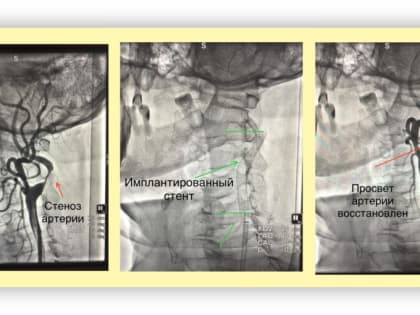

Новые технологии в медицине: рентгенохирургические методы в Кинешме

Кинешемская ЦРБ внедряет современные методы диагностики и лечения.